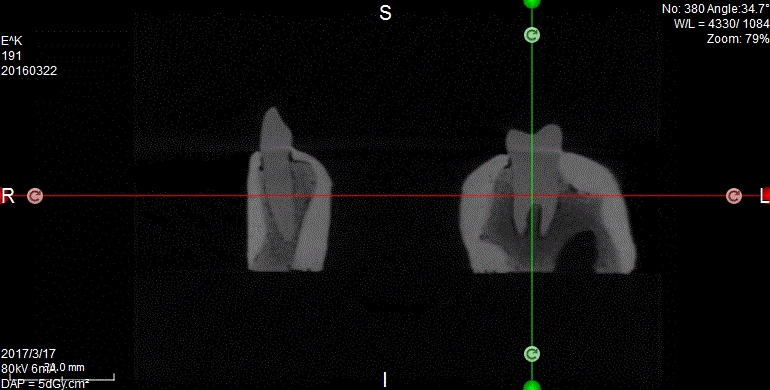

Oferujemy również szablony chirurgiczne przeznaczone do szkoleń z implantacji. Umożliwiają planowanie leczenia implantologicznego i przeprowadzenie szkoleń z wykorzystaniem plików CT, STL oraz druku 3D. Oferujemy nasze modele do szkoleń implantologicznych wraz z plikami DICOM i STL.

Pliki do wykonania szablonów można pobrać z naszej strony internetowej. Możemy je również dostarczyć wraz z modelami. Pliki te dostępne są dla modeli 10-1030, 10-3040, 10-3050, 10-5070,